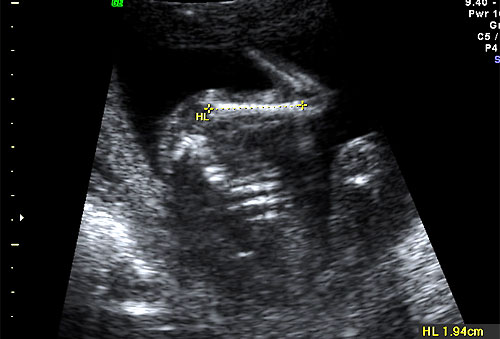

Normal 16 week HL measurement |